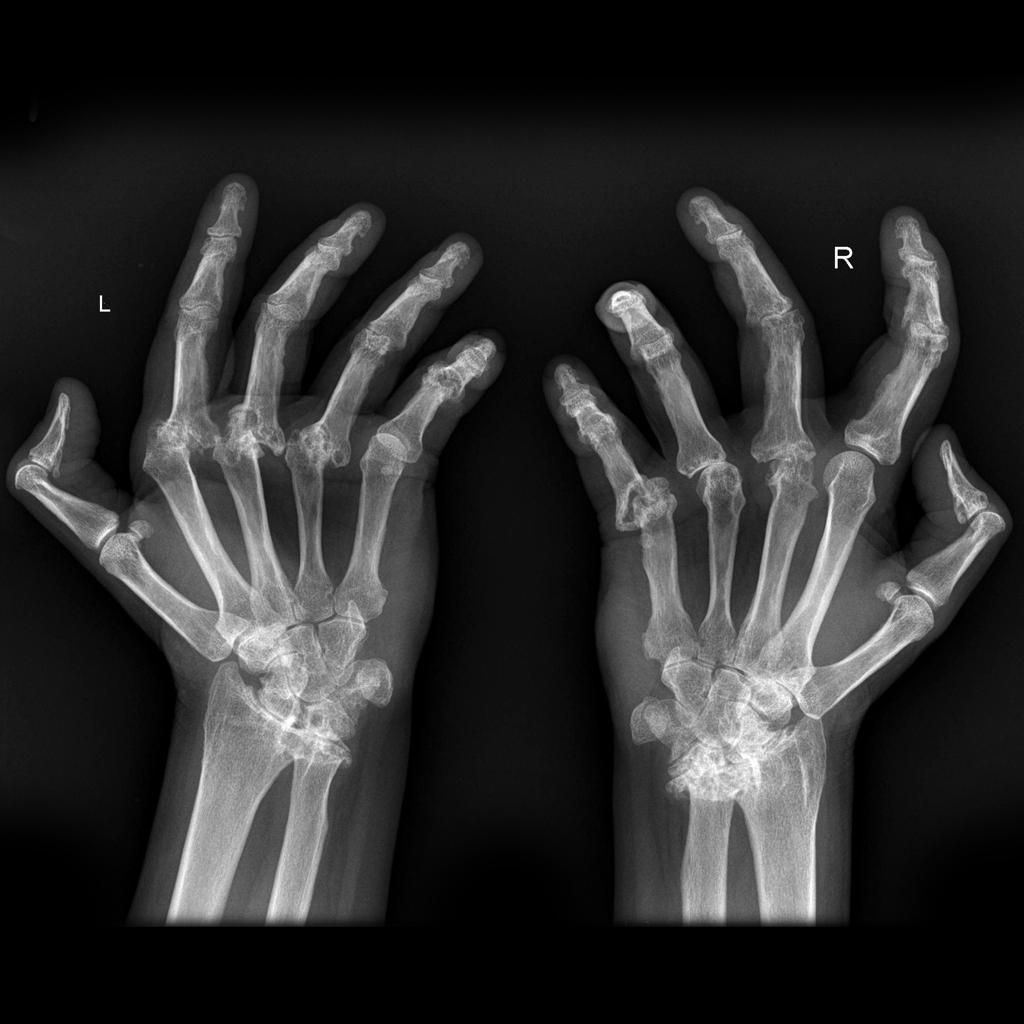

Radiographic hallmarks of RA

Earliest radiographic findings of RA

soft tissue swelling and peri-articular osteopenia (reflects synovitis and hyperemia)

First erosions to occur in the hand in RA patients

Bad RA in the hands

RA